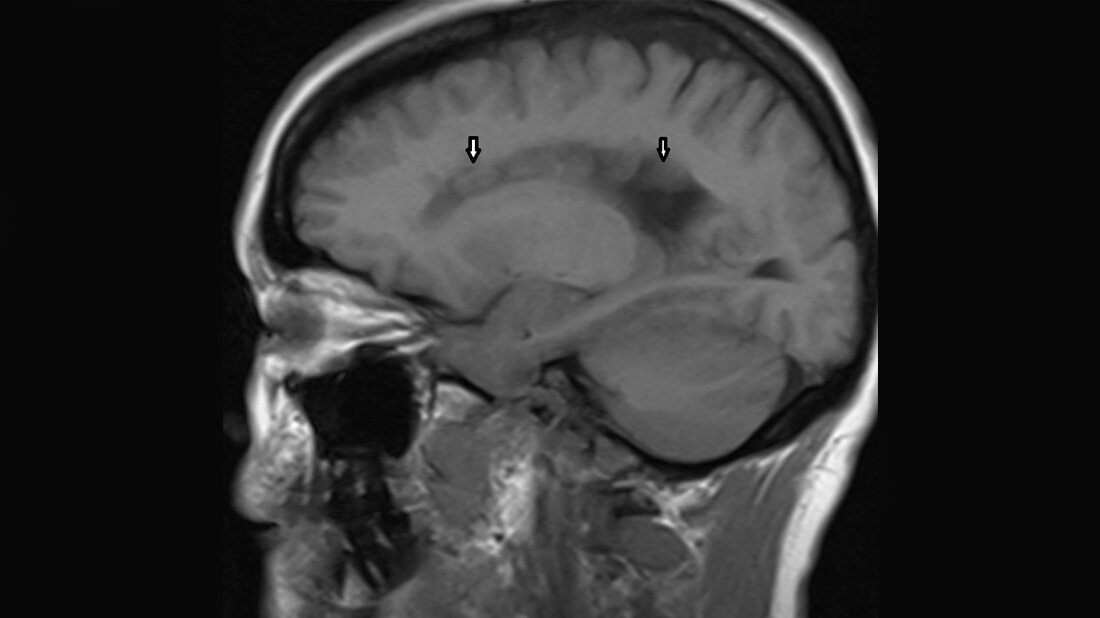

Anomalien und Normvarianten – Zerebrale Malformation 1.7: Heterotopie

Die Heterotopie ist die am häufigsten vorkommende Anomalie der kortikalen Entwicklung. Die Migrationsstörungen führen klinisch oft zu epileptischen Anfällen, die psychomotorische Entwicklung der subependymalen Heterotopie ist normal. Es werden 3 unterschiedliche Formen unterschieden.

Heterotopia is the most frequently occuring anomaly affecting cortical development. Neuronal migration disorders often clinically characterized by epileptic seizures as well as normal psychomotor development in many cases of subependymal type. There are three different types.